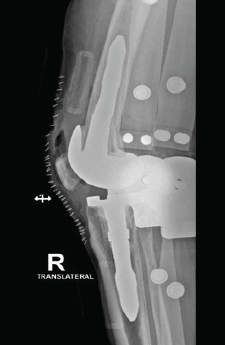

Wheelchair to Walking: Quadruple Arthroplasty of Hip and Knee Joints in a Patient with Severe Ankylosing Spondylitis

Remington C. Crossnoe , Varun M. Trivedi , Sterling J. DeShazo , Reagan L. Crossnoe ………………………………p.227-232